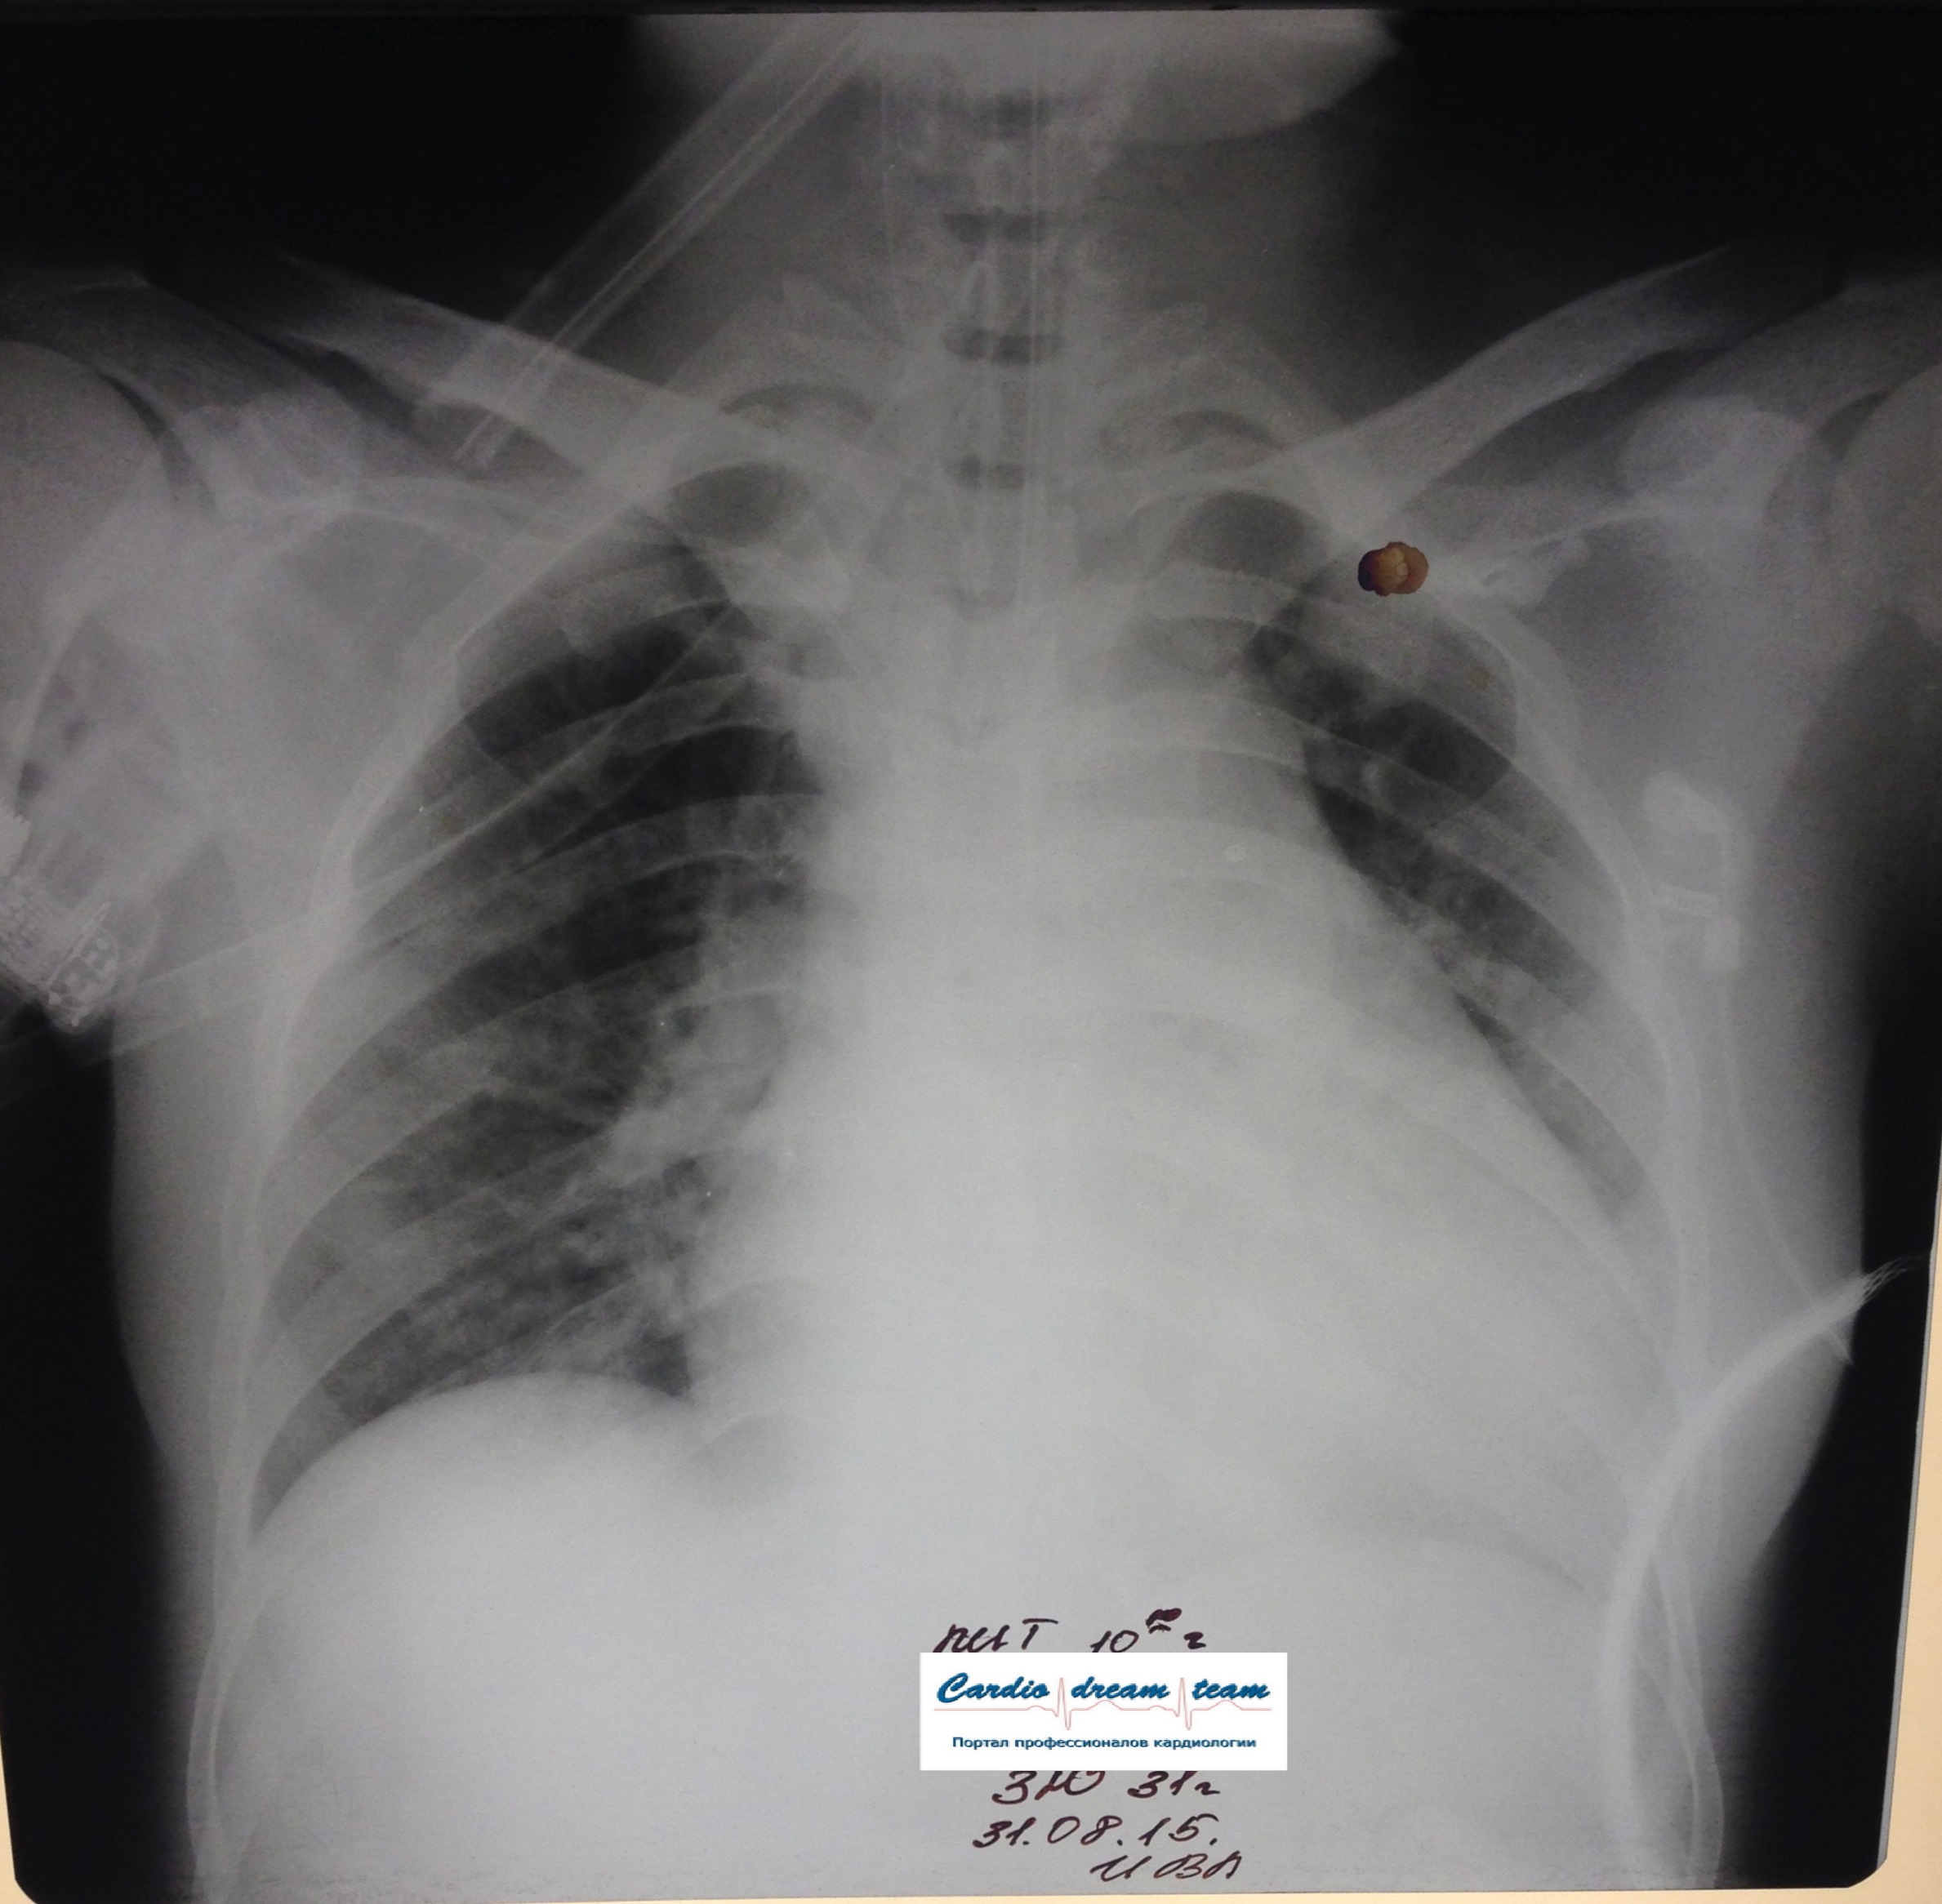

Динамика пневмонии у мужчины 67 лет с миеломной болезнью

Вложения:

1-.jpg

1-.jpg [ 1.24 MiB | Просмотров: 53307 ]

2-.png

2-.png [ 6.42 MiB | Просмотров: 53307 ]